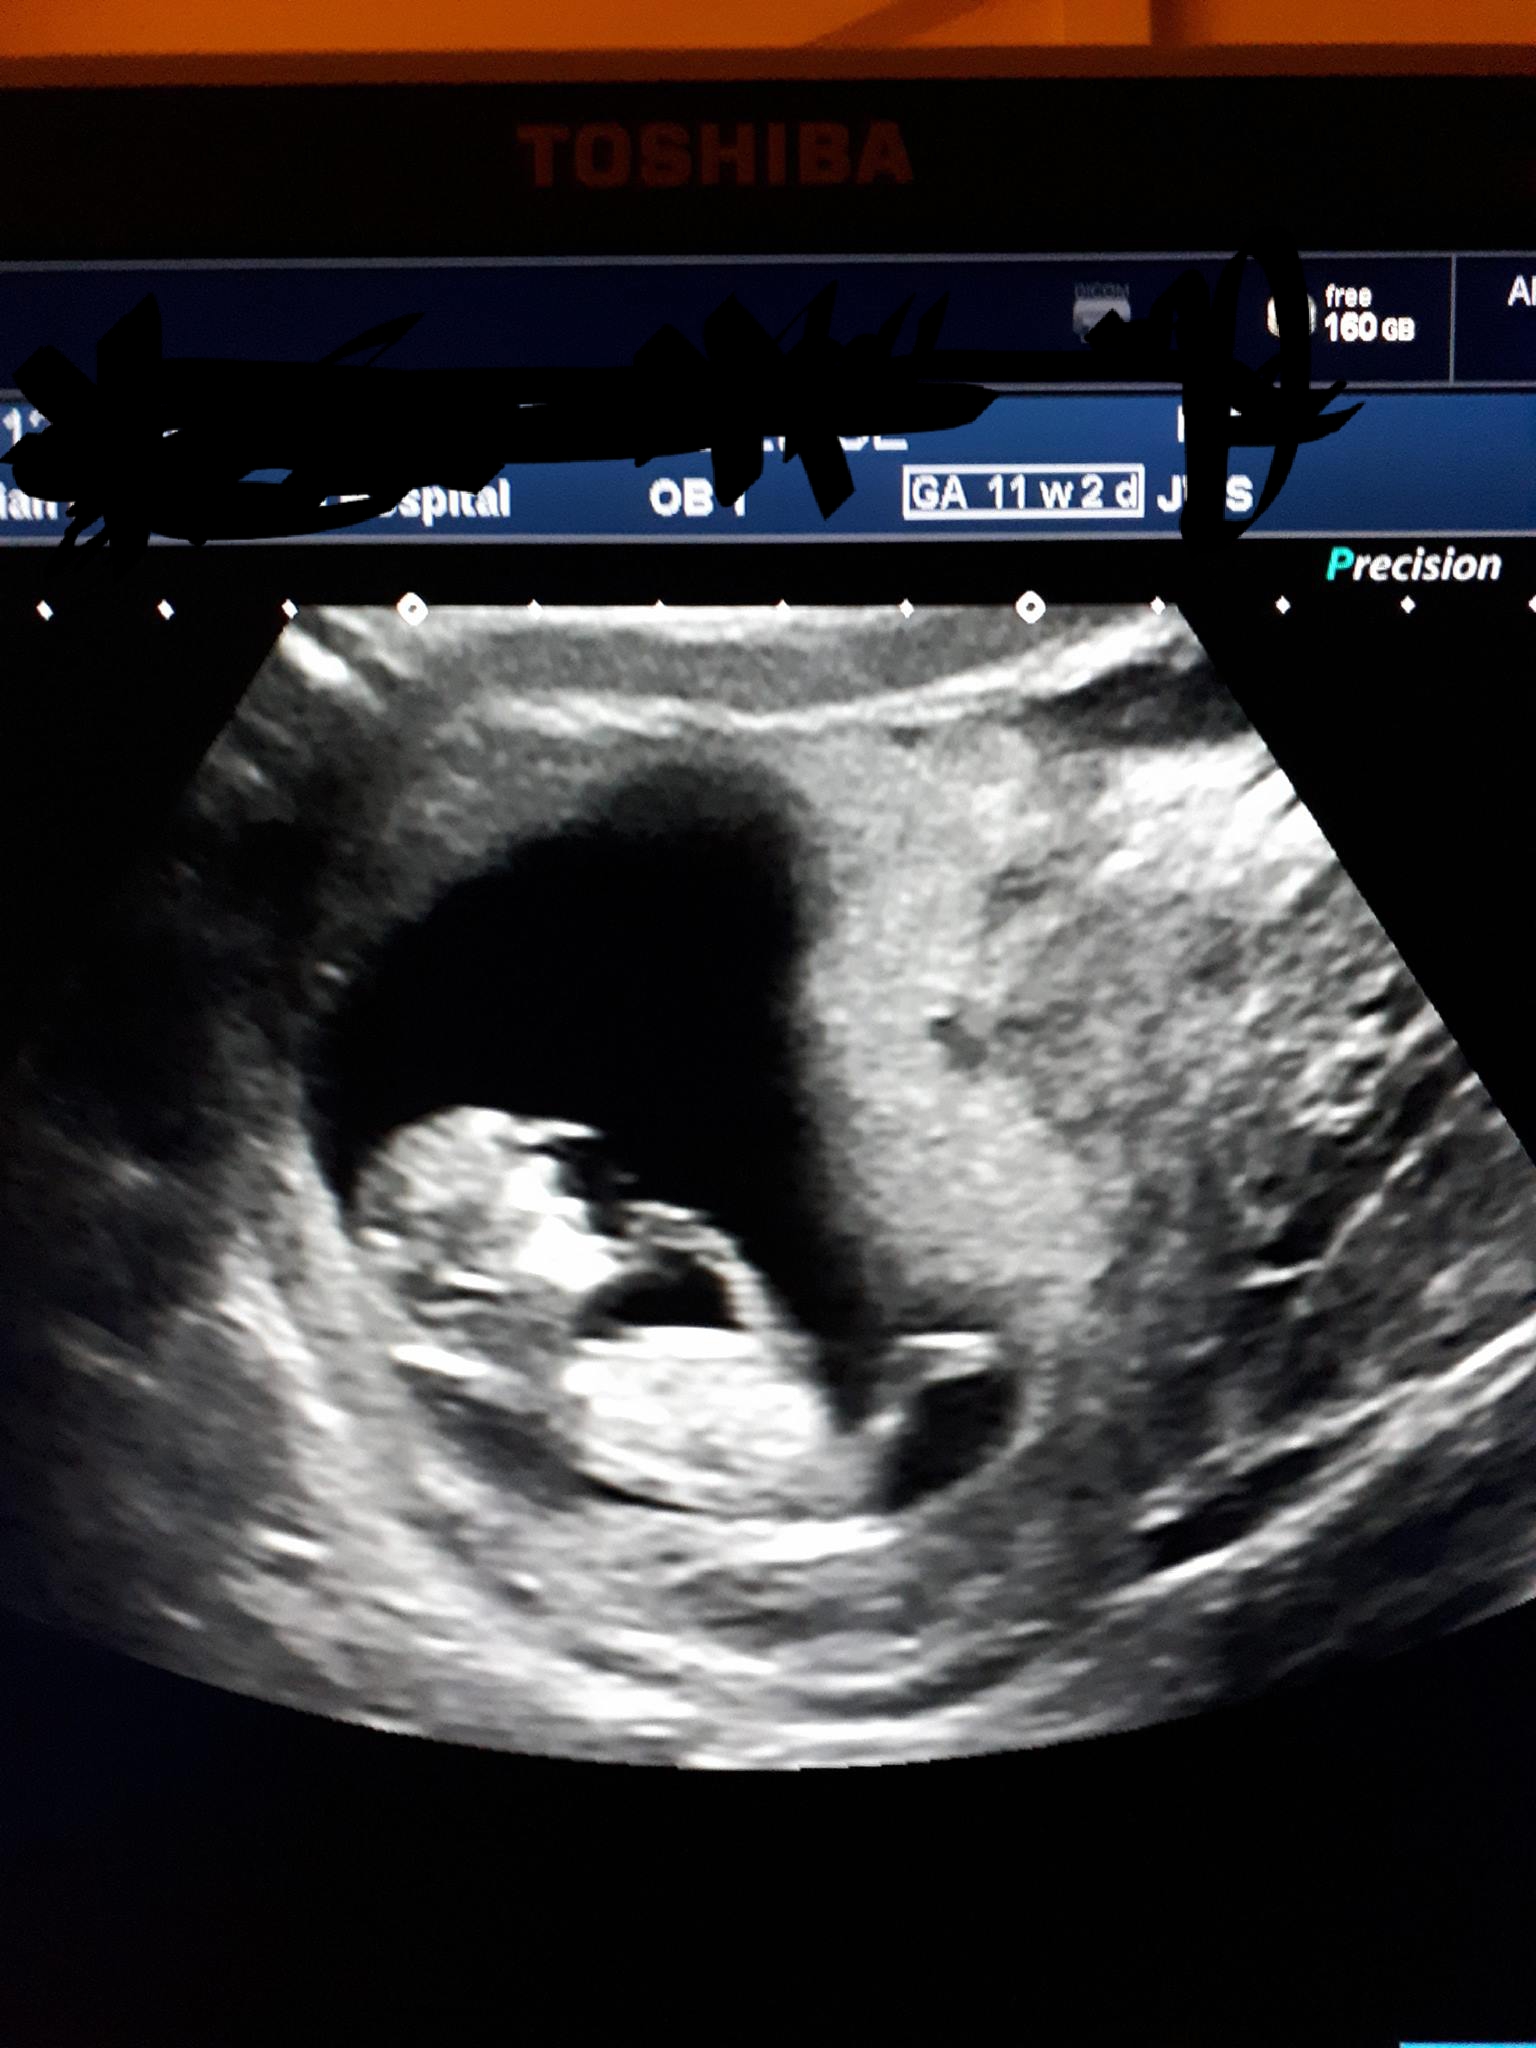

Attachment 38160Attachment 38161Attachment 38162

Ramzi has been debunked and 11 weeks is too early for a nub guess, sorry. If you happen to get a nub shot between 12-13 weeks, I'd be happy to guess!